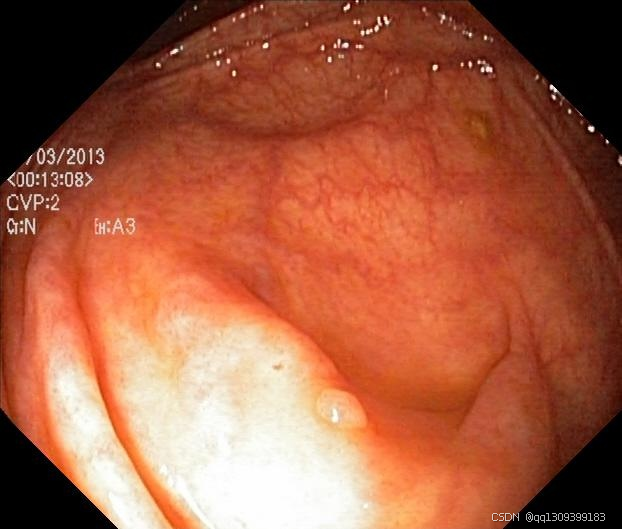

应用演示图示

在这里插入图片描述